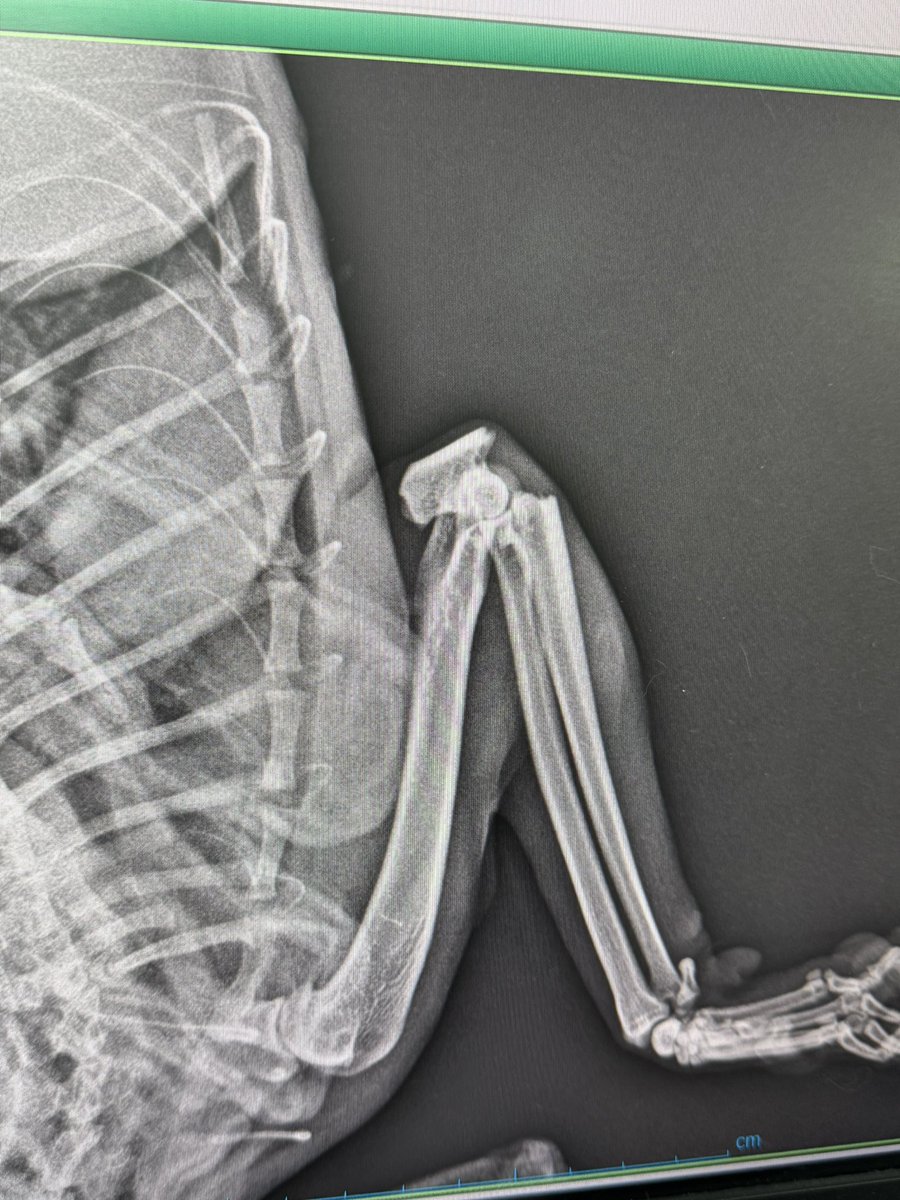

ACİL Bu çocuğu iki bacağı kırık sokakta buldular. Çok ağrısı var ve arka bacak kırığı kötü durumda. Bacağı kaybetmemesi için çok acil ameliyata girmesi gerekiyor. 20 bin tl ücreti var. Destek olmak için lütfen mesaj atın. Detayları da vereceğim.